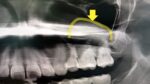

- 定期健診レントゲンで見つかった意外なものとは成城の歯科医院 ファーストデンタルクリニックの平澤です。 今回は定期健診にいらして下さっている30代男性に見つかった意外な物のお話です。 この患者さん定期健診に来て下さっているのですが、1年ぶりにレン… 続きを読む: 定期健診レントゲンで見つかった意外なものとは